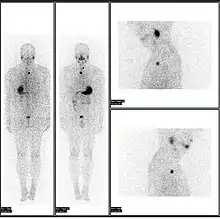

A nuclear medicine whole body bone scan. The nuclear medicine whole body bone scan is generally used in evaluations of various bone-related pathology, such as for bone pain, stress fracture, nonmalignant bone lesions, bone infections, or the spread of cancer to the bone.

Nuclear medicine myocardial perfusion scan with thallium-201 for the rest images (bottom rows) and Tc-Sestamibi for the stress images (top rows). The nuclear medicine myocardial perfusion scan plays a pivotal role in the non-invasive evaluation of coronary artery disease. The study not only identifies patients with coronary artery disease; it also provides overall prognostic information or overall risk of adverse cardiac events for the patient.

A nuclear medicine parathyroid scan demonstrates a parathyroid adenoma adjacent to the left inferior pole of the thyroid gland. The above study was performed with Technetium-Sestamibi (1st column) and iodine-123 (2nd column) simultaneous imaging and the subtraction technique (3rd column).